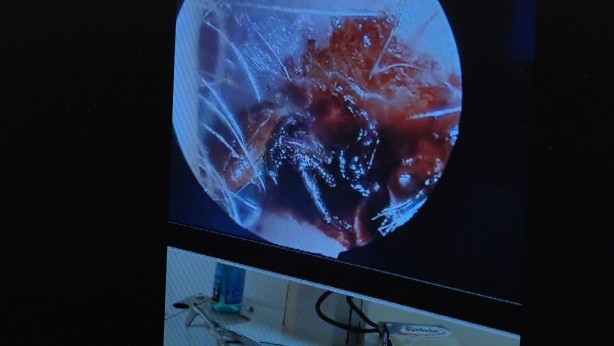

70 yaşındaki kadının kulağında hareket eden kene görüldü

Bitlis’in Tatvan ilçesinde 70 yaşındaki kadın hastanın kulağına giren kene başarıyla çıkartıldı. Tatvan ilçesinin bir köyünde yaşayan 70 yaşındaki kadın hasta, sabah uyandığında kulağında bir şeylerin hareket ettiğini hissetti. Tatvan Devlet Hastanesi acil servisine başvuran kadın hasta, doktorların kulağında hareket halinde olan keneyi tespit etmesinin ardından Kulak Burun Boğaz Hastalıkları Uzmanı Operatör Dr. Hakan Tuhan’a sevk etti. Op. Dr. Hakan Tuhan, kısa süreli operasyonla 70 yaşındaki kadın hastanın kulağında hareket halinde olan keneyi başarıyla çıkarttı. 10 gün boyunca takibi yapılan hasta sağlığına kavuşarak taburcu oldu.